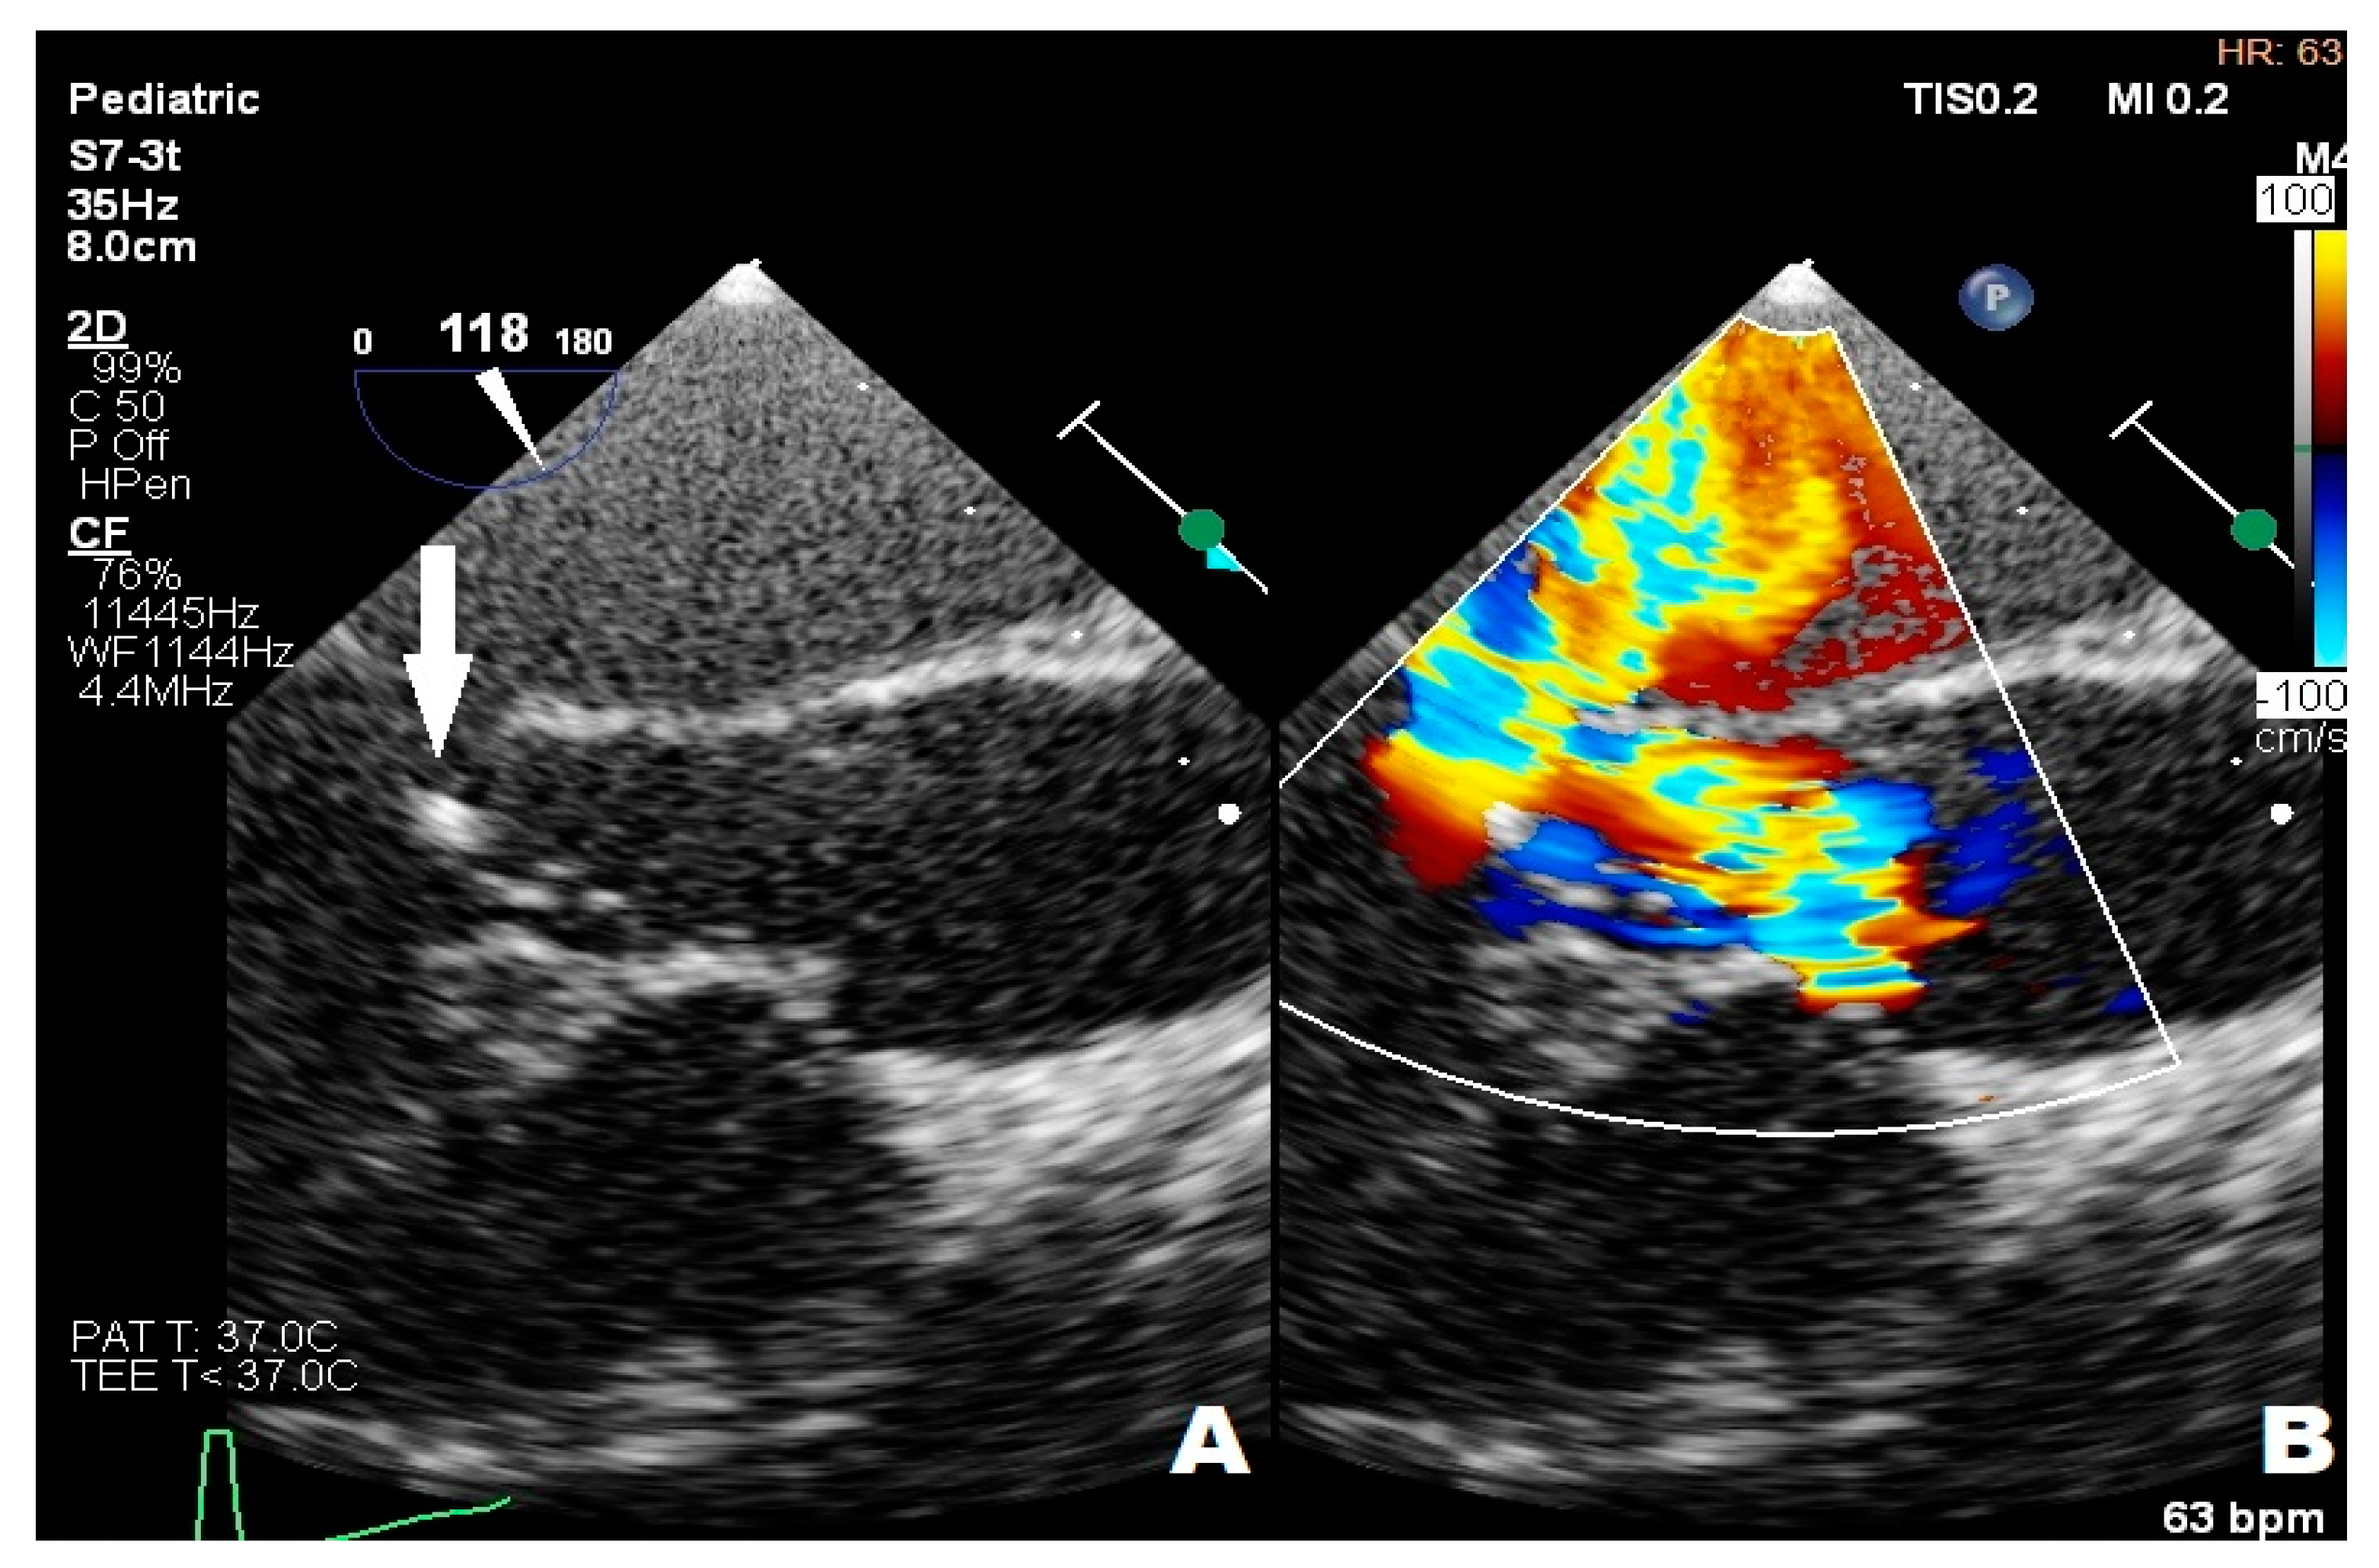

3.3. Case 3